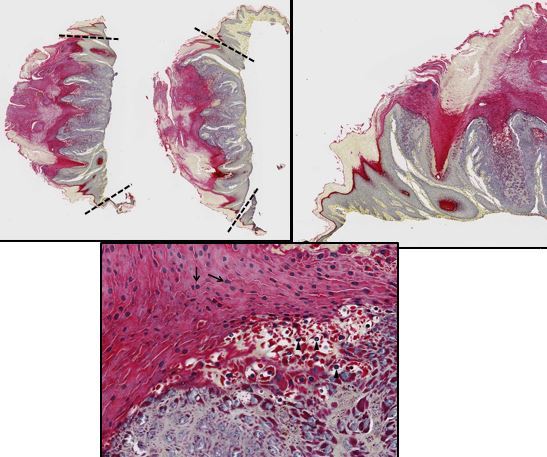

Carcinome épidermoïde